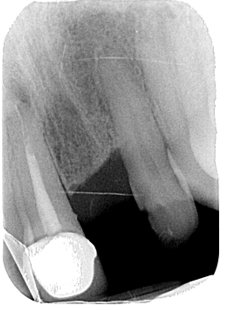

• Peri-apical lesion UR1 seen on radiograph

• RCT carried out 10 years ago

• Asymptomatic

CBCT scan OF UR1 Site, peri-apical cyst?

• Is the lesion healing vs active disease?

• Strict criteria is no periapical area present after rct. The meta-analyses had indicated that using strict criteria for judging treatment success, a minimum follow-up period of 3 years (Ng et al., 2007)